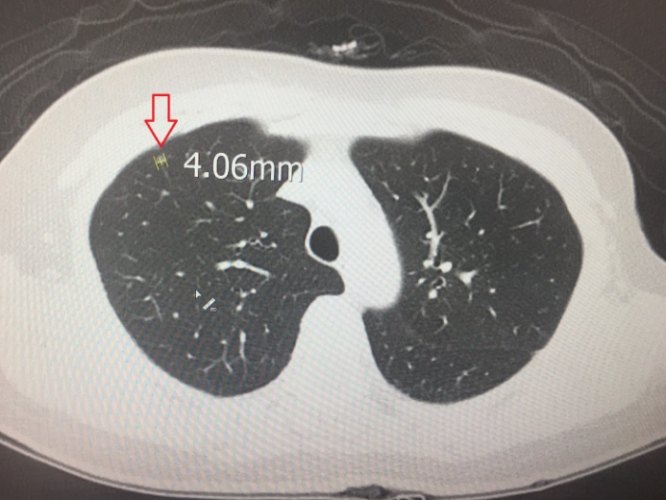

這是個很實際的問題!醫學上評估毛玻璃結節生長速度,常用的一個概念是「體積倍增時間」(Volume Doubling Time, VDT)。白話講,就是這個結節體積長大到兩倍所需要的時間。實心的惡性肺結節,VDT可能短到一、兩個月;而純毛玻璃結節(非實心部分),如果是惡性的,它的毛玻璃結節生長速度通常慢得多,VDT常常超過400天,甚至好幾年!這種特性也解釋了為什麼純毛玻璃結節常常可以安全地追蹤觀察。一個典型的例子:追蹤兩年了,結節幾乎沒變大,這種毛玻璃結節生長速度就讓人安心不少。

第一次發現一個小的純毛玻璃結節,我通常會建議3-6個月後再做一次低劑量電腦斷層。為什麼是這個時間點?就是要抓它可能的毛玻璃結節生長速度。如果它真有問題(而且是那種長得比較快的),幾個月通常能看出變化了。如果這次複查沒變化,下次間隔可能拉長到一年,甚至更久。這個時間表的依據,核心就是對潛在毛玻璃結節生長速度的評估與防備。

當追蹤過程中觀察到結節有「不良變化」時,積極的毛玻璃結節治療——通常是手術切除——就會擺上檯面。這些變化包括:結節尺寸明顯變大(特別是實心成分增加)、密度變濃、形態變得不規則、邊緣出現毛刺等。一般來說,對於持續存在超過2年、尺寸大於8-10毫米、特別是含有實心成分(部分實性結節)的毛玻璃病變,醫生會更傾向評估手術的可能性,因為它們是早期肺癌的風險較高。手術方式現在主流是微創的胸腔鏡手術,切除範圍力求精準(肺楔形切除或肺節切除),儘量保留健康肺組織。

- 持續存在、>8-10mm的純毛玻璃結節:風險增加,醫生會更仔細評估,若追蹤有變化(如變大、密度增加)或病人焦慮度高,可能考慮切除。

- 部分實性結節(就是混合毛玻璃和實心成分的):這是風險最高的類型!如果實心成分持續存在且>5-6mm,或者整個結節>10mm,特別是在追蹤中發現它在長大、實心部分變多,醫生通常會強烈建議手術切除。記住,尺寸是參考,最終還是要看毛玻璃結節生長速度變化、影像形態變化趨勢以及個人風險來決定。